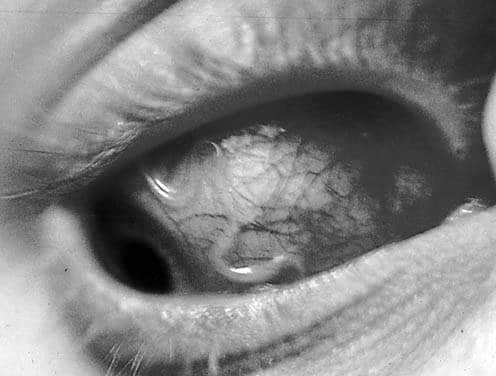

Если взглянуть на фотографии людей, страдающих от паразитарного заражения глаз, можно заметить явное присутствие червя в глазном яблоке. Это зрелище выглядит довольно неприятно.

Если гельминт располагается в центре глазного яблока, его могут заметить окружающие. Это состояние значительно сказывается на психоэмоциональном состоянии пациента, вызывая депрессию и неврозы.

Внешний вид. Взрослые особи (макрофилярии) беловатого цвета с характерным для нематод габитусом. Самцы достигают длины 30-35 мм и примерно 0,4 мм толщины, самки — длины 40-70 мм и 0,5 мм толщины. Длина личинок (микрофилярий), покрытых оболочкой, составляет всего 300 мкм.